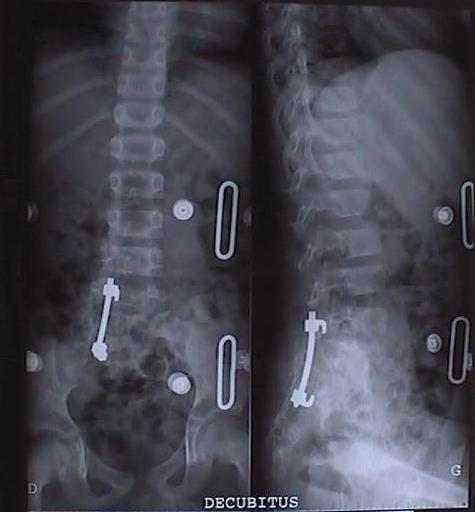

Quand ces anomalies se présentent à un très jeune âge et entraîne une scoliose, il n’y a parfois que la chirurgie qui permet de trouver une solution. Nous vous proposons un cas très particulier d’une hémi-vertèbre droite semi-segmentée L5 fusionnée en S1 avec lyse isthmique et densification des bords L4 gauche chez un enfant de 7 ans : L’histoire de O’Malay (né en 1995)O’Malay, de dos le 13 décembre 2000 La raison pour laquelle la maman de O’Malay amène son fils chez l’ostéopathe, c’est parce qu’il se tient mal ! Dès le déshabillage, le simple fait de mettre O’Malay devant la glace quadrillée montre qu’il y a effectivement un quelque chose d’anormal. La photo est parlante par elle-même. Il est proposé à la maman de faire une radiographie de l’ensemble de la colonne (full spine) et de la région lombaire, face et profil. C’était le 13 décembre 2000. En voici les résultats.Radio de profil : Hémi-vertèbre droite de L5Radio de face de L 5Radio de profil de L 5Radio du bassin de faceRadio de trois quarts : droit & gauche Un scanner est effectué en 2001, dont la technique comporte une acquisition hélicoïdale de 3 mm avec des reconstructions 2 D et 3 D.Scanner avec acquisition hélicoïdale La conclusion est nette : « On retrouve l’hémi-vertèbre droite semi-segmentée L5 fusionnée en S1. II s’y associe une lyse isthmique avec densification des bords L4 gauche (vertèbre sus jacente) ».Scanner avec reconstruction en 3 DDécision chirurgicale Une décision chirurgicale est prise avec comme indication : « résection de l’hémivertébre par doubles voies d’abord pour éviter le déséquilibre progressif qui va s’accentuer petit à petit avec la croissance ». L’intervention chirurgicale se passe très bien. La voie d’abord antérieure est privilégiée avec dissection du muscle psoas droit et résection triangulaire de l’hémi-vertèbre.La voie d’abord postérieur est ensuite réalisée : ablation complète de l’hémi-vertèbre et mise en place d’un matériel avec crochet sur le trou sacré de S2 et sur la lame de L4. Un greffon osseux est mis en place aussi bien en avant qu’en arrière.Un corset de maintien lombaire sera porté pendant 4 mois. La mise debout est progressive. Un contrôle radiologique est effectué pour vérifier la position de la colonne vertébrale, celle du matériel et du greffon.Contrôle radiologique postopératoireMise en route… La mise en position debout ne se fait pas comme prévu : Une sciatalgie droite est diagnostiquée avec « douleurs suspendues au niveau du creux poplité, variable dans sa symptomatologie au cours des journées d’hospitalisation ».La douleur disparaît en position allongée et revient dès la reprise de la marche.Un IRM est pratiqué sans résultat. Le retour à la maison est effectif 10 jours après l’intervention avec une prescription d’antalgiques. Dès le lendemain, les douleurs dans le membre inférieur s’aggravent en position debout au point que la marche est impossible. La maman prend sur elle d’aller revoir l’ostéopathe. En fait, O’Malay souffre d’une psoïte aiguë, avec signe du héron manifeste et une perte complète de confiance dans son membre inférieur droit. Un traitement ostéopathique tissulaire est entrepris au niveau de la cicatrice antérieure, ce qui permet de soulager la douleur de la cuisse.La douleur de type sciatalgie, diagnostiquée à l’hôpital est provoquée par une hyper-contracture des ischio-jambiers qui servent à maintenir l’enfant debout, genou plié.Un ré-apprentissage de la marche se fait progressivement dans la foulée à genoux de manière ludique.Progressivement, O’Malay passe des pleurs au sourire puis, tout à coup, ce sont des éclats de rire. La partie semble gagnée. La maman appelle le lendemain au téléphone pour annoncer triomphalement que son fils est debout et marche normalement.Cette photo a été prise le 14 octobre 2002Chapeau au médecin orthopédiste ! En consultant l’ensemble du dossier de cet enfant, né en 1995, on ne peut que dire « chapeau » au chirurgien orthopédiste qui a pris la responsabilité d’opérer.

Ce ne devait pas être évident et quand on voit les résultats, on ne peut qu’approuver sa décision.